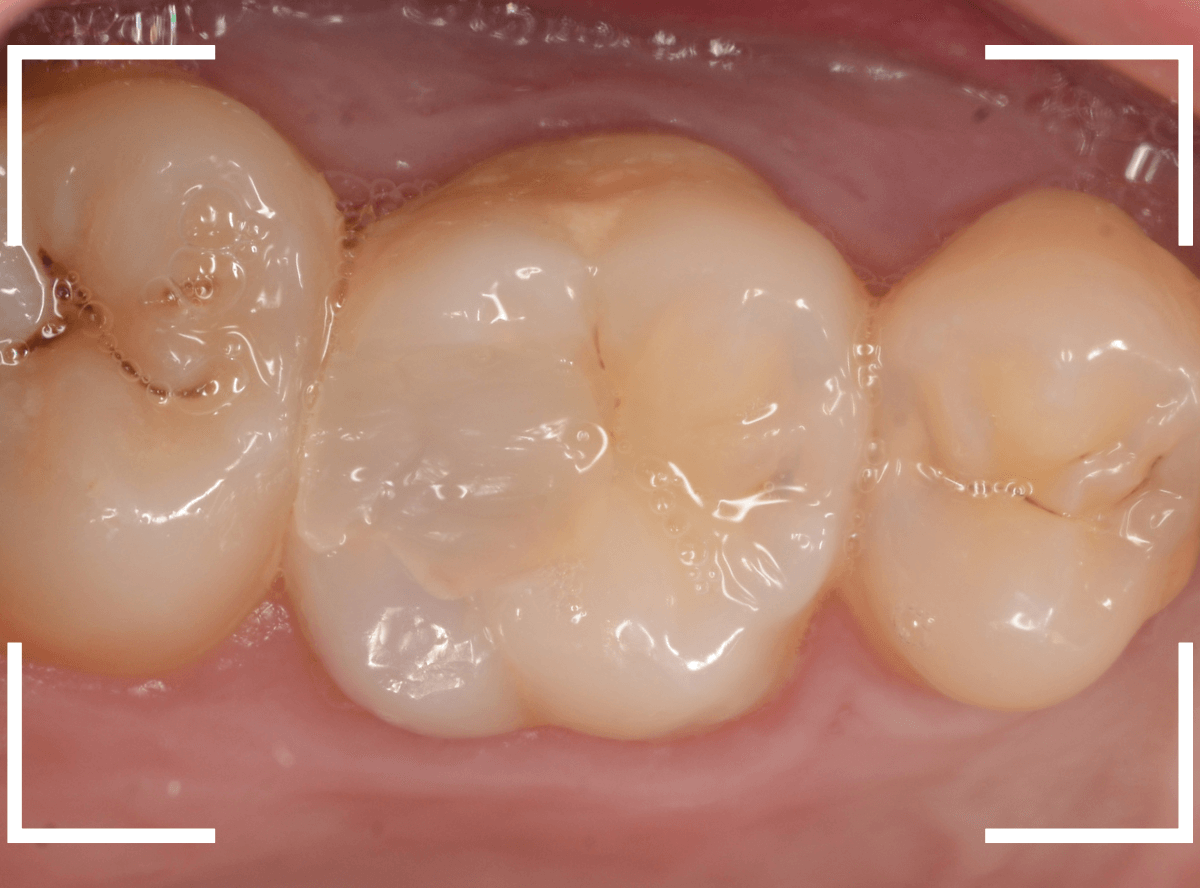

Case.13 問題なさそうなレジンの下で深い虫歯

他の歯の治療希望で来院された患者さんで、レントゲンで大きな虫歯が見つかった方です。

以前に虫歯を削って、レジンをつめる治療がしてあります。

表面を見る限り、特に問題はなさそうです。

まずは、麻酔をしてつめ物を慎重に外してみます。

両歯とも、色々嫌な予感のする所見です。

レジンを除去して虫歯を調べます。

赤い部分が虫歯です。

少しずつ虫歯が出てきました。

慎重にレジンを外して、全ての虫歯を除去しました。

レントゲンから予想される通り、かなり大きな虫歯でした。

症状が出る前に治療が出来て良かったです。